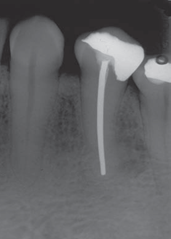

What material is shown in this xray? (related to endo)

•Silver points – more radiopaque than gutta percha, first used in 1930. Not used today because it can undergo tarnish and corrosion and staining.

•Gutta-percha – less radiopaque than the silver points